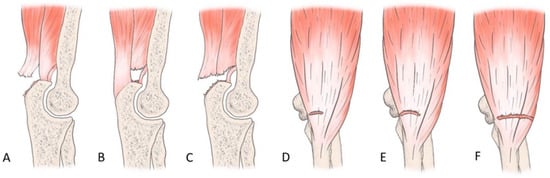

The most common tendon injuries are rotator cuff tears of the shoulder, hand flexor injuries, and achilles tendon injuries [1]. Triceps tendon rupture is the least reported among all the tendon injuries in the literature [2,3]. 65 years ago, Anzel evaluated a series of 1014 patients with tendon ruptures in various locations, and triceps tendon ruptures accounted for only 0.8% of this series [4]. Currently the prevalence is increasing, and the prevalence of triceps tendon injuries has been found to be 3.8% [5]. Theoretically, the types of tendon injuries are tendon avulsion or inside the muscle belly. In practice, a rupture almost always occurs in the area of the tendon-bone junction, and the cause is an eccentric contraction of the triceps causing a tendon deformity of more than 8% [6]. Traditionally the triceps tendon has a uniform attachment to the olecranon ulnae. This premise has caused problems in assessing the degree of damage in traumatic triceps tendon ruptures. In 2006, an anatomic study by Madsen confirmed that in most cases the medial head of the triceps has a single attachment to the olecranon ulnae [7]. This insertion is located in a deeper layer and forms a narrower part of the attachment, and very rarely is only this part damaged [8]. The long and lateral head of the triceps has a common attachment that runs more superficially, gradually extending laterally into the surrounding area towards the musculus anconeus, which helps to strengthen the bone-tendon junction. The width of the attachment correlates with the size of the olecranon and ranges from 20 to 40 mm. Paradoxically, the thickness of the tendon is not as pronounced. The attachment itself occupies a large surface area, reaching 400 mm2 in diameter and is dome-shaped [9]. These current findings are particularly important in partial tendon ruptures when a decision has to be made whether to proceed conservatively or with surgical revision. MRI is an appropriate method of choice to accurately assess the current condition. A schematic representation of the three basic types of partial DTTR rupture can be seen in Figure 1, while the normal anatomic attachment relationships of the triceps tendon in sagittal section to the olecranon ulna and a sub-complete rupture of the triceps tendon of the right hand are shown in Figure 2 and Figure 3. Furthermore, the place of attachment of the individual heads of the triceps to the olecranon ulnae is presented in Figure 4.

Figure 1. Illustration of the three basic types of DTTR partial rupture. (A): “Superficial tear”—the tendinous portion of the lateral and long head of the triceps (B): “Deep tear”—the deep muscular portion of the distal triceps involving the medial head of the triceps (C): “Full body tear”—a sub complete tear of the DTTR. (DF)—coronal planes showing partial, complete, and lateral involvement [10].